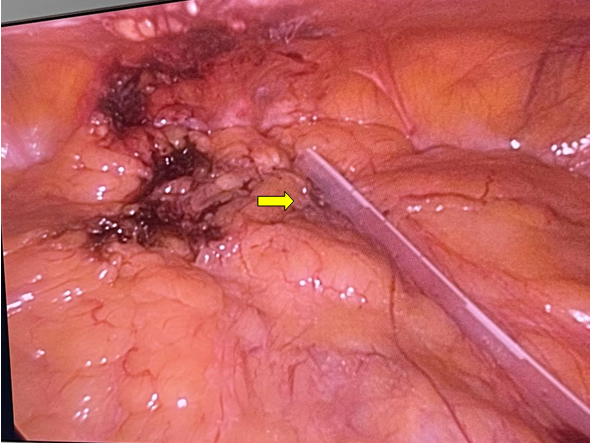

大网膜与腹壁及盆腔入口广泛粘连(黄色箭头所指为黏连部位)

分离大网膜后将腹透管送至理想位置(黄色箭头:腹膜透析导管尖端置入腹腔内入盆位置)